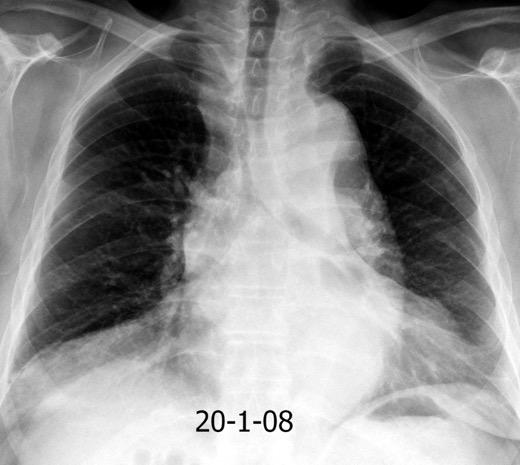

Triada de Garland

Ganglios paratraqueales derechos e hiliares bilaterales

95% de pacientes tienen ganglios hiliares bilaterales aislados o con afectación mediastínica (espec. paratraqueal derecho).

Criado E et al. Pulmonary sarcoidosis: typical and atypical manifestations at high-resolution CT with pathologic correlation. Radiographics. 2010